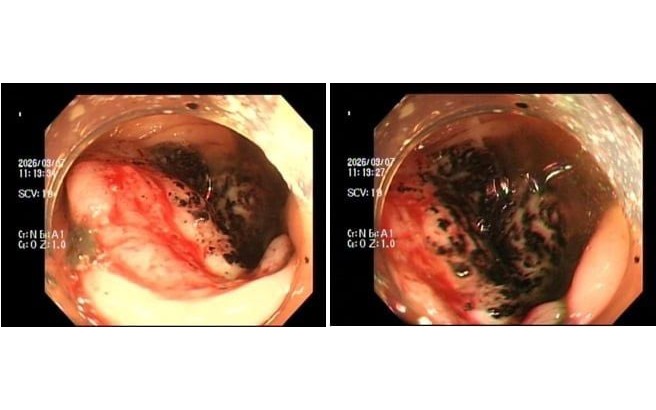

Ảnh minh họa